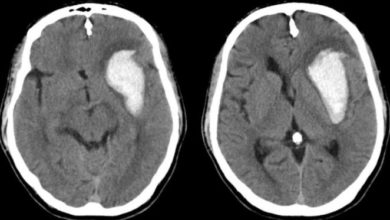

Subdural-Epidural Kanama

Kafatası kemiğinin altında beyni koruyan ‘’Dura’’ adı verilen bir zar vardır.Kafatası kemiği ile Dura arasında bir kanama varsa (Dura’nın üstündeyse)…